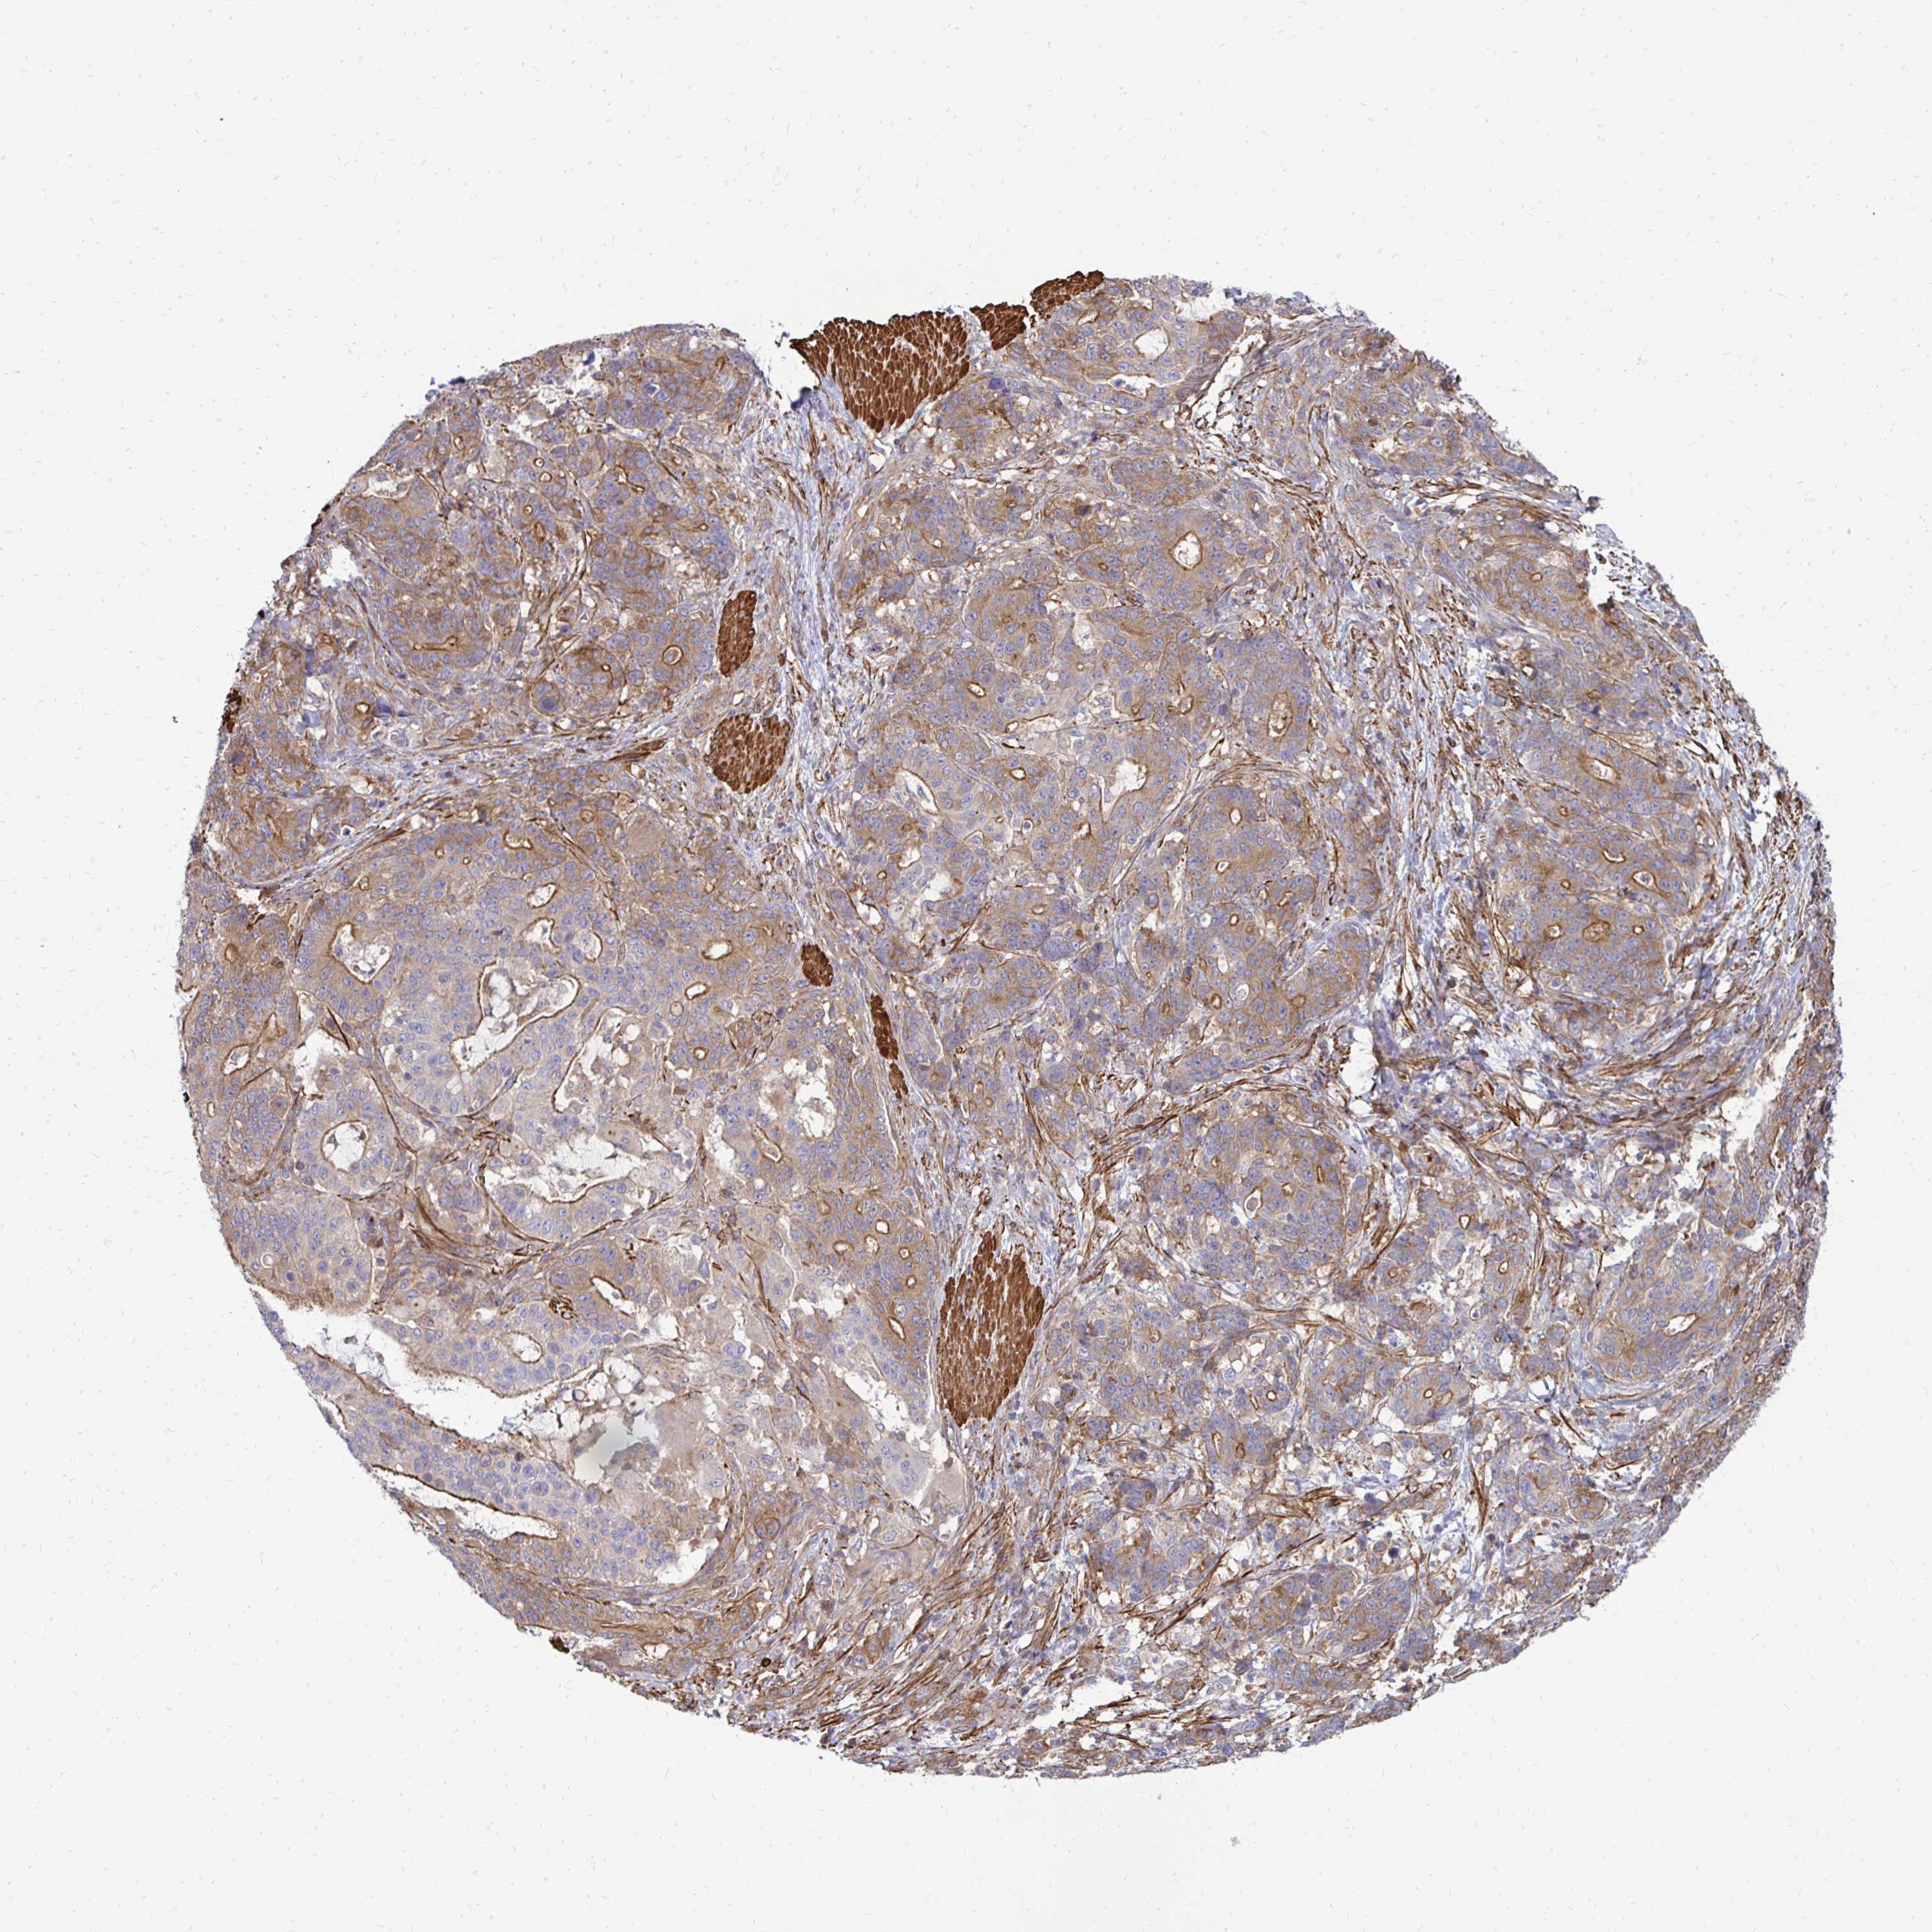

STOMACH CANCER - Protein expressioni

A mouse-over function shows sample information and annotation data. Click on an image to view it in a full screen mode. Samples can be filtered based on level of antibody staining by selecting one or several of the following categories: high, medium, low and not detected. The assay and annotation is described here.

Note that samples used for immunohistochemistry by the Human Protein Atlas do not correspond to samples in the TCGA dataset.

Antibody stainingi

Antibody staining in the annotated cell types in the current human tissue is reported as not detected, low, medium, or high, based on conventional immunohistochemistry profiling in selected tissues. This score is based on the combination of the staining intensity and fraction of stained cells.

Each image is clickable and will lead to virtual microscopy that enables deeper exploration of all samples and also displays staining intensity scores, fraction scores and subcellular localization as well as patient and tissue information for each sample.

Antibody HPA051322

Antibody CAB017111

Staining

High

Medium

Low

Not detected

Intensity

Strong

Moderate

Weak

Negative

Quantity

>75%

75%-25%

<25%

None

Location

Nuclear

Cytoplasmic/membranous

Cytoplasmic/membranous,nuclear

Adenocarcinoma, NOS

Adenocarcinoma, High grade